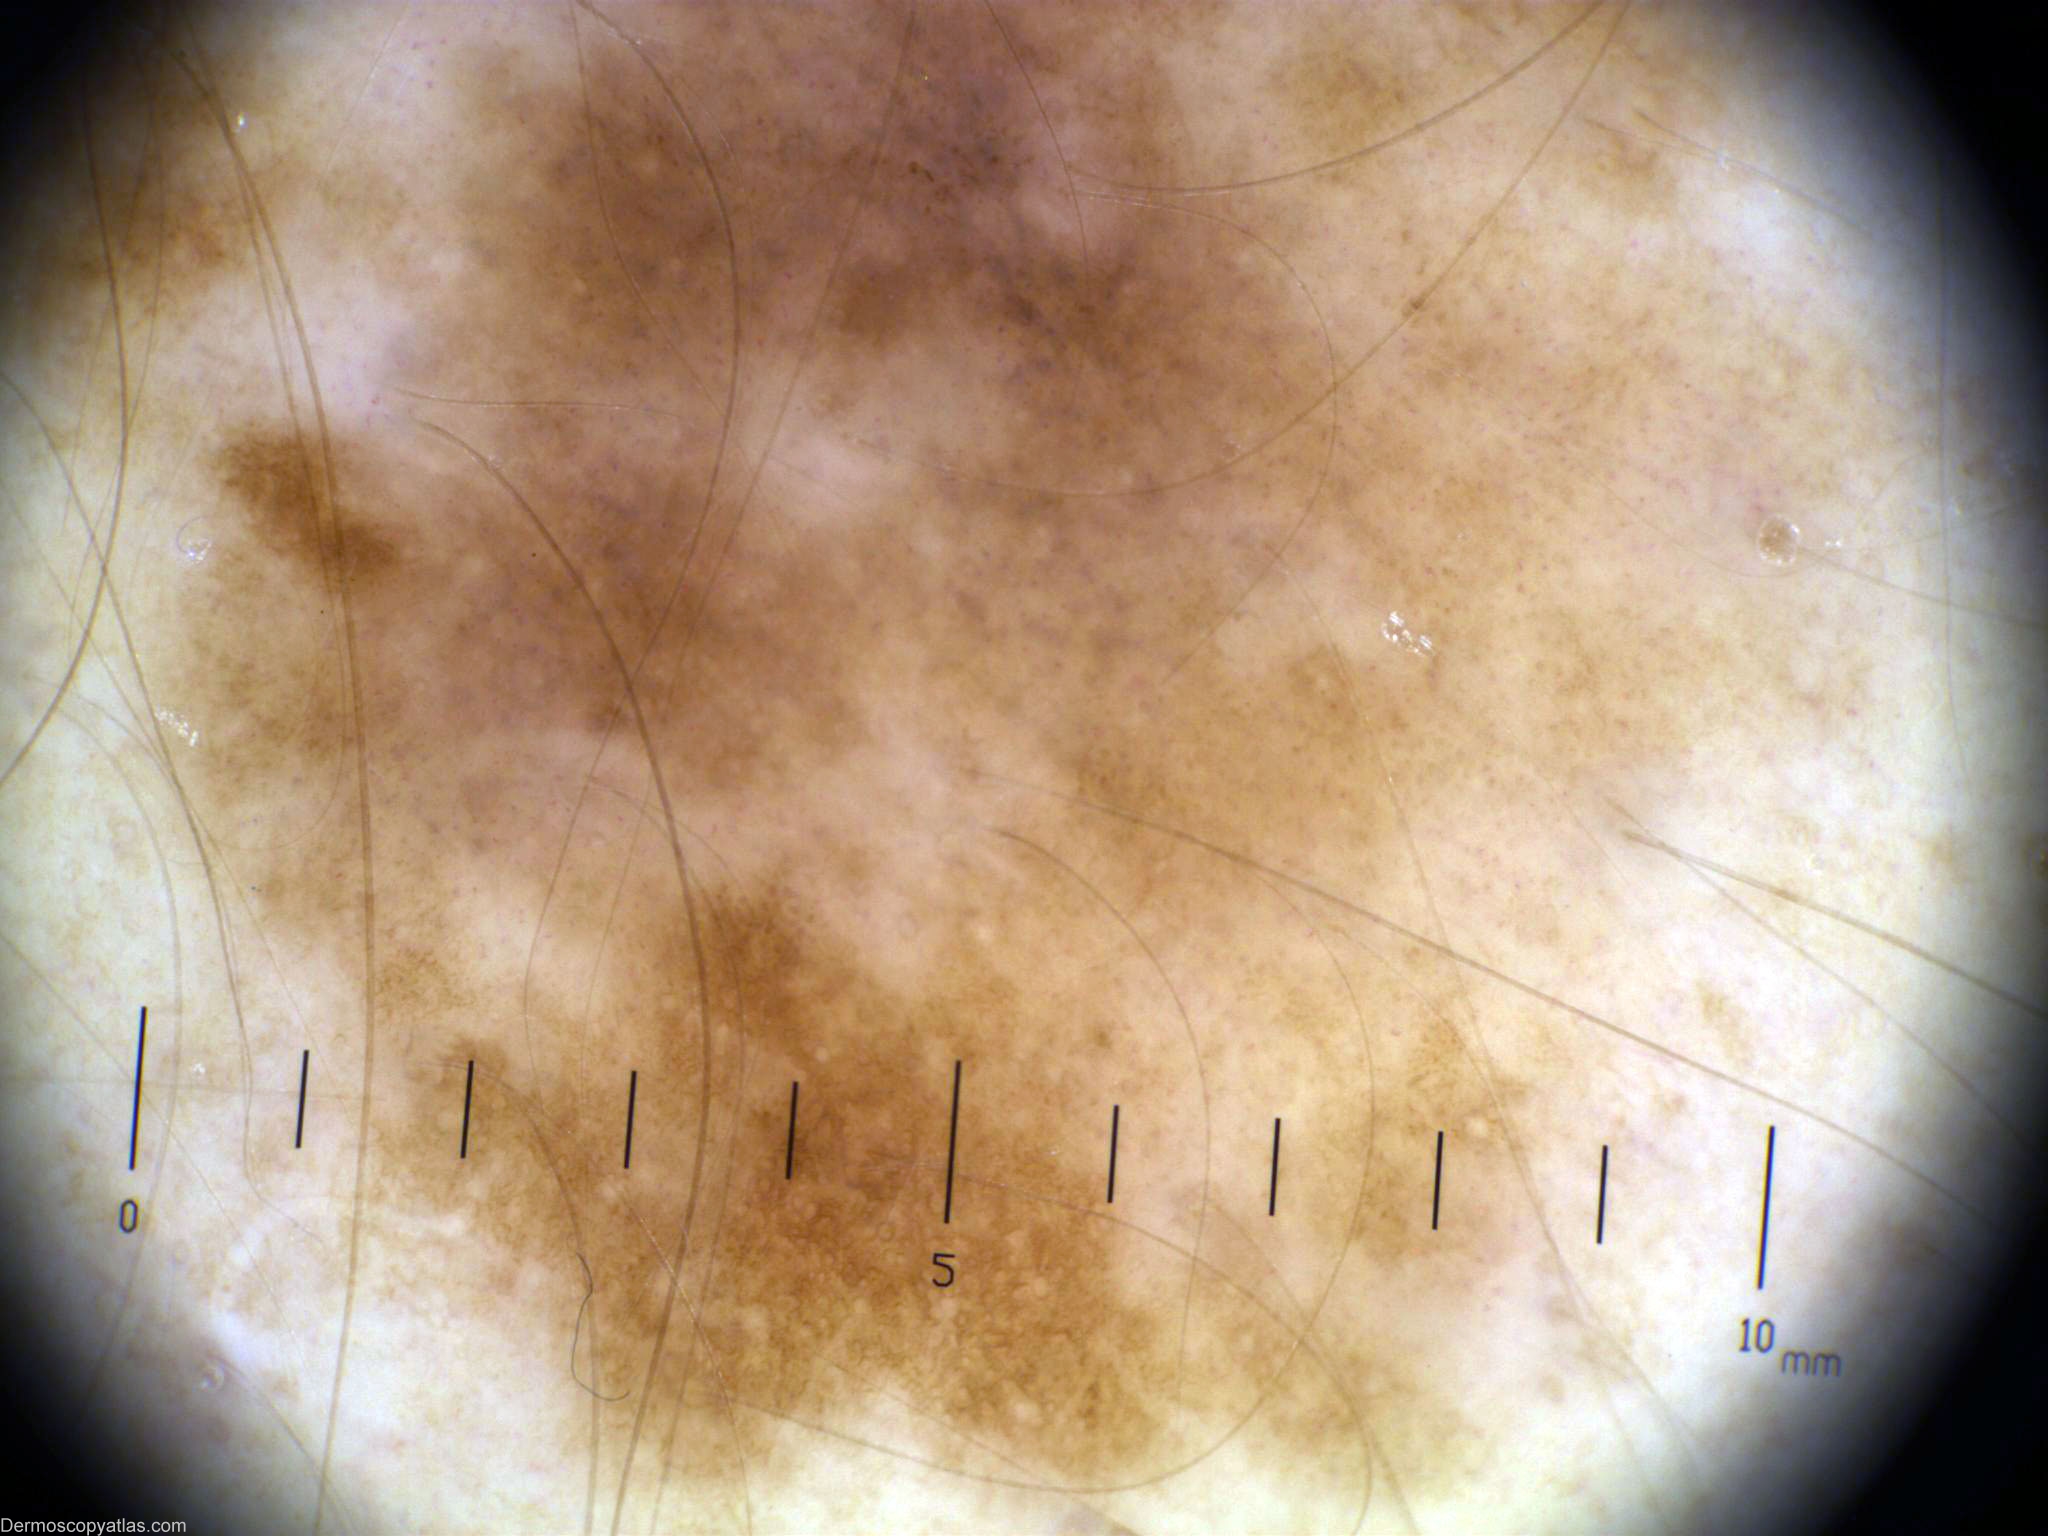

Diagnosis - Melanoma in situ